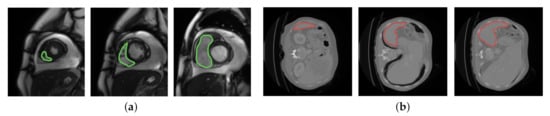

| Null | Null | Colon | SST | - | |||

| Our Algorithm | SST | ||||||

| Null | Null | Liver | SST | - | |||